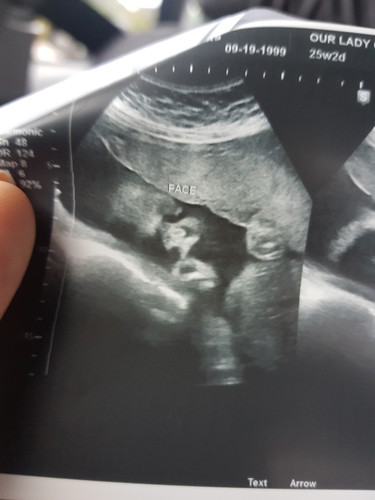

Hello mommies!! Share ko lang binigyan nako ni ob ng request for ultrasound and finally nakapag pa ultrasound ako kanina! Hehehe it's a boy! Nakakatuwa din kasi nagpakita talaga sya, kitang kita face nya kahit hindi naka 4D ?? 25weeks pregnant here ?

mom of aden miguel